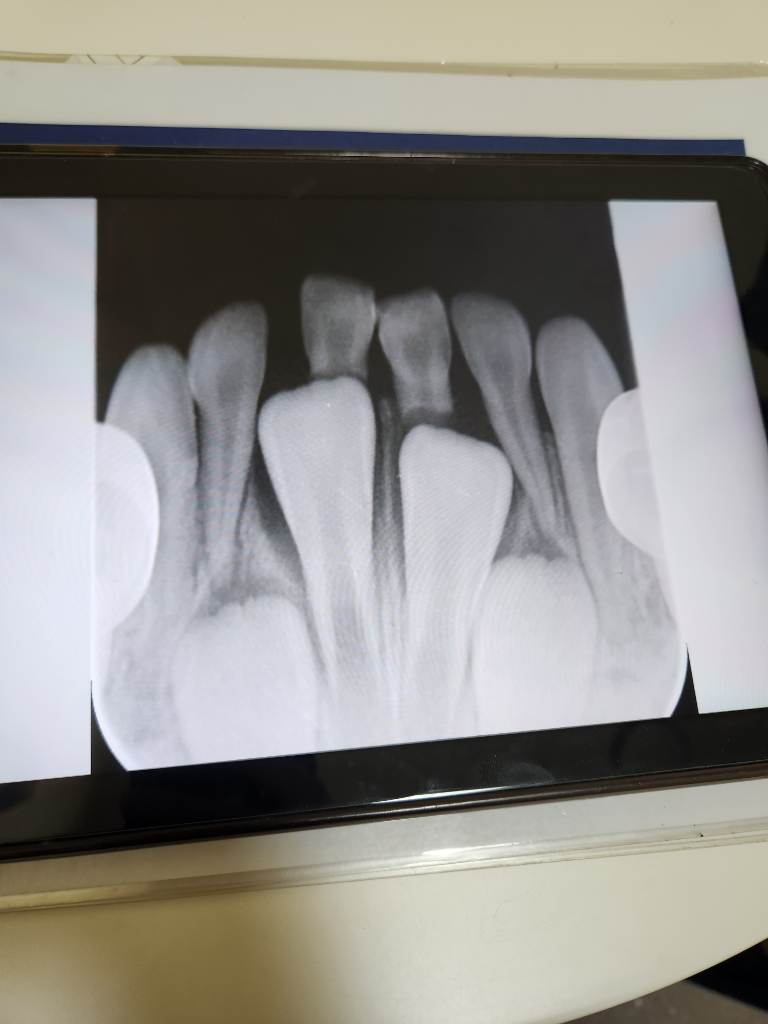

첫발치인데 2개만뺏어요 그런데 2개를 더빼라고하시는데 빼야할까요?(다시질문드려요)

아랫니 b a a' b' 중에 a이가 많이흔들려서 치과에 갔어요~~그런데 치아 잇몸이라고해야되나요 너무좁아서

영구치하나가. 유치 한개 반정도를 차지해서요

4개를 다뽑아줘야 올바로 자리잡을수있다고 하시더라구요 사진상보면 맞는 말씀이신데 .. 4개 한 번에 뽑을 자신이 없고 정보도 없어서

일단 aa'만 뽑고왓거든요~~ bb'도뽑는게 맞을까요 아님 둿다흔들리면 뽑을까요

b랑b'는 안흔틀리는 상황이라 마취가필요합니다~ 미리뽑아주는게좋은가요 기다릴까요

아직 B번 치아는 발치를 안하셔도 될것같습니다. 조금더 기다리시는게 좋을것같으니 조금더 기다리셧다가 발치를 하세요.